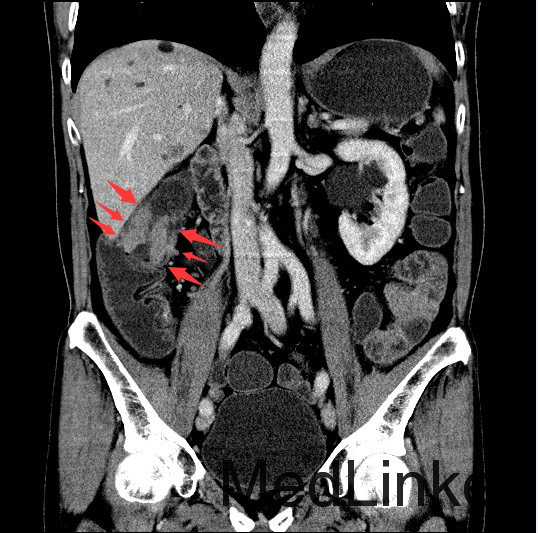

查体:腹平,腹软,肝区、双肾区无叩痛,腹部移动性浊音(-)。肠鸣音4次/分。双下肢无浮肿。 辅查:全腹螺旋CT平扫+增强:1、结肠肝区病变,考虑结肠癌,累及全层。2、直肠及乙状结肠病变,考虑炎症性病变。

讨论:本病例可以在CT冠状位看到结肠肝曲肠壁局限性增厚,属于浸润型结肠癌的表现,CT诊断结肠癌的时候,一般冠状位能够较好的显示结肠全貌,可以比较容易发现病灶,因此平常应先从冠状位发现胃肠道的病灶,再结合横断位诊断。作为影像医生除了报告癌肿,还需要注意一些临床关注的问题,比如癌肿与周围组织的关系,局部有无肿大淋巴结转移,其他脏器有无浸润或转移,在报告中提示这些情况,能够帮助临床选择合适的治疗方案。